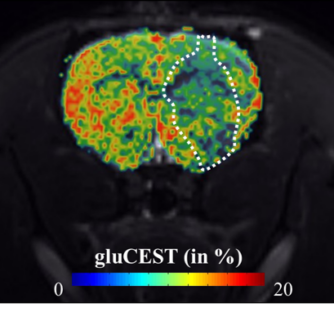

Visualiser la réactivité astrocytaire par IRM GluCEST